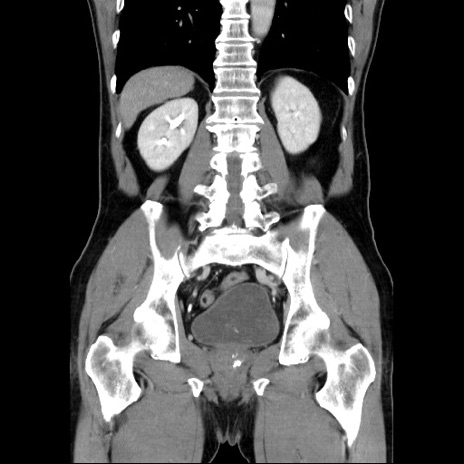

症例34(冠状断像)

【症例】60歳代 男性

【主訴】右鼠径部膨隆

【現病歴】1年程前より右鼠径部膨隆あり。自己にて還納可能だったため放置していた。3時間前より右鼠径部の脱出を認め、還納困難となり受診。

【既往歴】高血圧

【身体所見】右鼠径部に小児頭大の膨隆あり。弾性硬であり、用手還納は困難。左鼠径部にも膨隆を認める。脱出はなし。

【データ】WBC 15500、CRP 測定なし